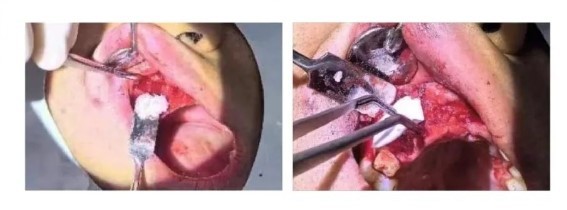

Preparation of nourishing holes and soft tissue debridement.

Performing Guided Bone Regeneration (GBR) with the implantation of Osseograft bone powder and a bone membrane.